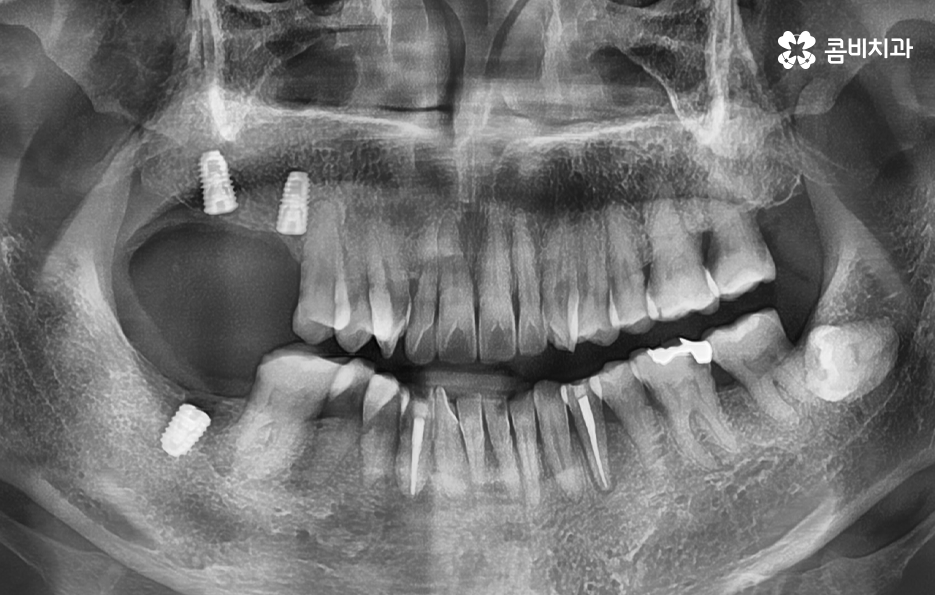

일반적인 임플란트의 치료 과정은 충치나 치주염 등으로 치아를 발치하게 되었을 때 치아 발치 후 잇몸이 아물고 회복되기를 기다리고 있는데요. 잇몸이 충분히 회복된 후에 임플란트를 잇몸 뼈에 식립하는 것을 시작으로 치과 내원과 어금니 임플란트 기간에 대해 대략적으로 알아보면 내원 횟수는 약 45회 정도로 예상되며 평균적으로 34개월 정도면 치료가 마무리 되고 있어요

여기서는 일반적인 치료 과정이라는 점을 전제로 하고 있는데요. 잇몸 뼈 상태가 양호하고 건강한 상태인 경우에 임플란트를 위한 치과 내원 횟수와 기간이 약 45회, 34개월 정도로 예상되는 것이며 잇몸 뼈의 상태가 좋지 않아서 뼈이식이 필요하거나 잇몸 이식술이 필요한 경우에는 치과 내원 횟수와 치료 기간이 더 늘어날 수 있는데요

임플란트의 원리 자체는 어떤 치료에도 비슷하게 적용되지만 치료 계획을 세우다보면 치아를 상실한 원인도 다르고 현재 잇몸 상태부터 전신 건강의 차이가 있기 때문에 세부적인 치료 계획이 달라지면서 임플란트의 치료 방법은 다양하게 적용되고 있는데요

예를 들어 20대에 충치로 치아 하나를 발치하게 된 사례와 60대 이후 노인분이 풍치로 인해 대부분의 치아를 잃고 전체임플란트를 해야 한다면 임플란트의 치료 원리 자체는 비슷해도 치료 계획은 전혀 달라지는 것과 비슷한 이치라고 볼 거예요